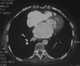

Calcification in heart

Calcification is the accumulation of calcium salts in a body tissue. It normally occurs in the formation of bone, but calcium can be deposited abnormally in soft tissue, causing it to harden. [Source: Wikipedia ]